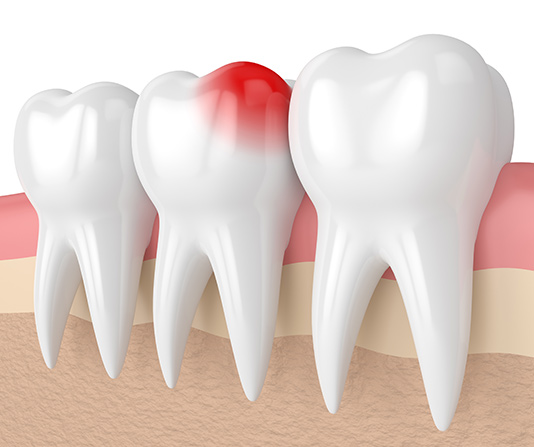

Dental implants restore your entire tooth, from root to crown, by being inserted directly into the socket. To maintain the bone's strength and health and to firmly anchor your new tooth in place, they fuse with the jaw. Implants are durable and frequently maintain their perfect state for a lifetime.